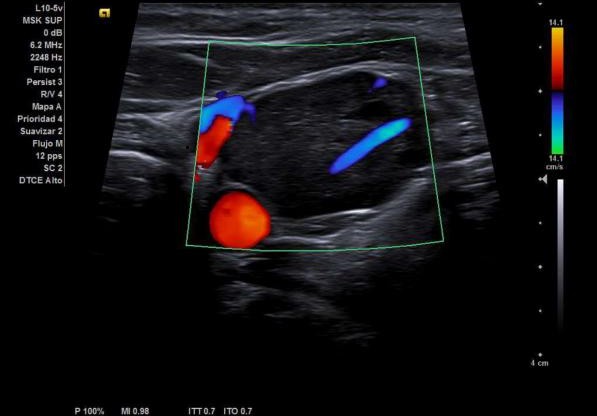

Dada la clínica y la exploración física, se decide realizar ecografía clínica en el Centro de Salud, con los siguientes resultados:

Este caso, destaca la importancia de la ecografía en la evaluación inicial de las tumoraciones cervicales en Atención Primaria. La identificación temprana de lesiones con características ecográficas de malignidad, como los procesos linfoproliferativos (entre ellos el linfoma), es clave para un tratamiento oportuno y mejora del pronóstico.